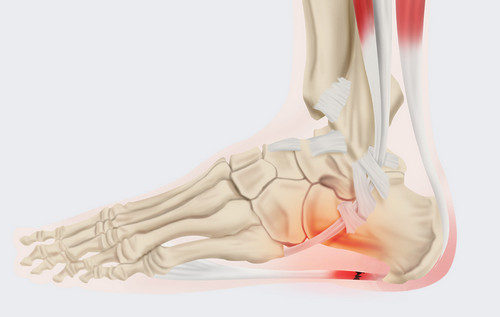

족저 근막염이란?

족저근막염은 발바닥 뒤꿈치에 염증이 생기면서 나타나는 통증을 말합니다. 남성보다 여성에게 약 2배 정도 더 많이 발생한다고 하며, 과도한 발의 스트레스나 무리한 운동이 주요 원인으로 알려져 있습니다. 이 밖에도 급격한 체중 증가나 평발 역시 발병 위험을 높이는 요인이 됩니다.

족저 근막염의 가장 흔한 증상은 아침에 통증이 특히 심하다는 점입니다. 밤사이 수축된 족저근막이 아침에 첫 발을 디디며 갑자기 늘어나 통증이 생기기 때문입니다. 대개 종아리 근육이 짧아지면서 발바닥 근막이 당겨져 발생하는 경우가 많습니다. 따라서 예방을 위해서는 평소 종아리와 발바닥을 함께 관리하는 것이 중요합니다. 이미 증상이 있다면 생활습관 개선과 더불어 필요에 따라 약물이나 의료적 치료를 병행해야 합니다.